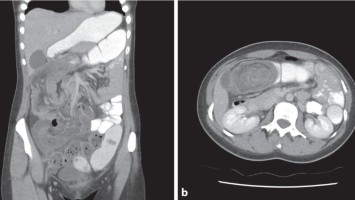

Alles weist auf eine Echinokokkose – doch das war es nicht

Die 29-jährige Patientin aus China stellt sich mit Appetitverlust und Druckgefühl im Abdomen vor. Obwohl sie weniger isst als zuvor, hat sie in den letzten Wochen 3 Kilo zugenommen. Der Ultraschall lässt schnell einen Verdacht für die Ursache ihrer Beschwerden aufkeimen: eine riesige polyzystische Raumforderung – typisch für eine Echinokokkose. Oder doch nicht? Eine englischsprachige Kasuistik.